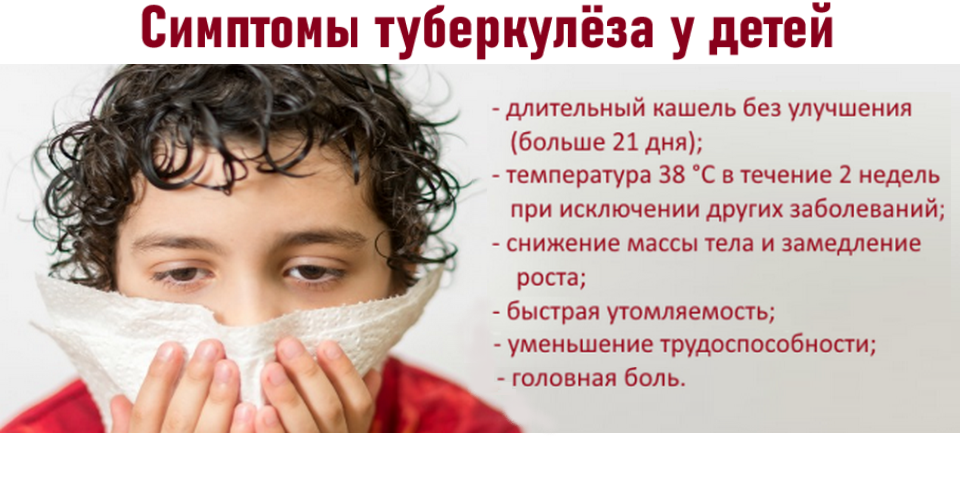

Симптомы туберкулеза: Как распознать и что делать

Раздел: Визуальные уроки